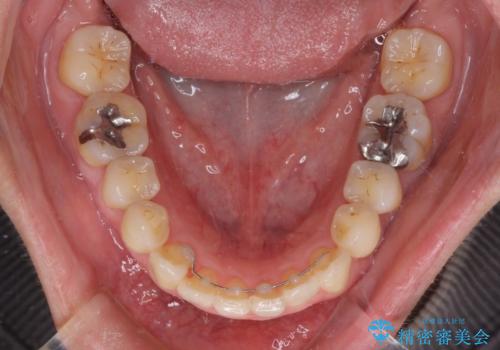

- 前歯のデコボコを気にして来院された患者様です。

上下前歯の先端同士が接触する切端咬合であったため、上顎は歯列を拡大し、下顎はIPR(歯と歯の間を削る)により叢生を解消しながら歯列を小さくすることとしました。

矯正装置にはインビザラインを用いることとしました。

治療途中に前歯に歯髄充血を思わせる痛みが認められたため、無理のない歯の移動と頻繁な経過観察を行いました。

切端咬合はスムーズに解消され、前歯の負担を軽減させることができました。